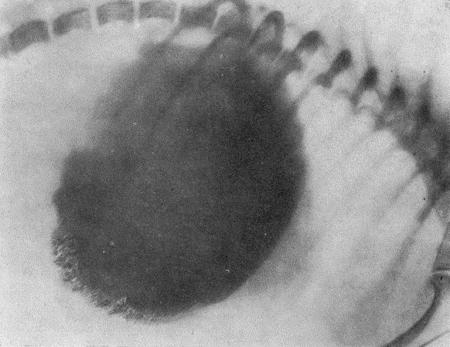

Болезни собак  - i_024.jpg

Рис. 24. Атрофический гастрит

Атрофический гастрит может быть диагностирован рентгенологически при наличии уплощения или даже полном исчезновении складок слизистой.

Однако следует иметь в виду, что не всякое утолщение складок будет соответствовать гипертрофическому гастриту и не всякое уплощение складок будет указывать на атрофический гастрит. Отсюда отрицательные данные рентгенологического исследования не могут служить доказательством отсутствия гастрита при наличии клинической картины.